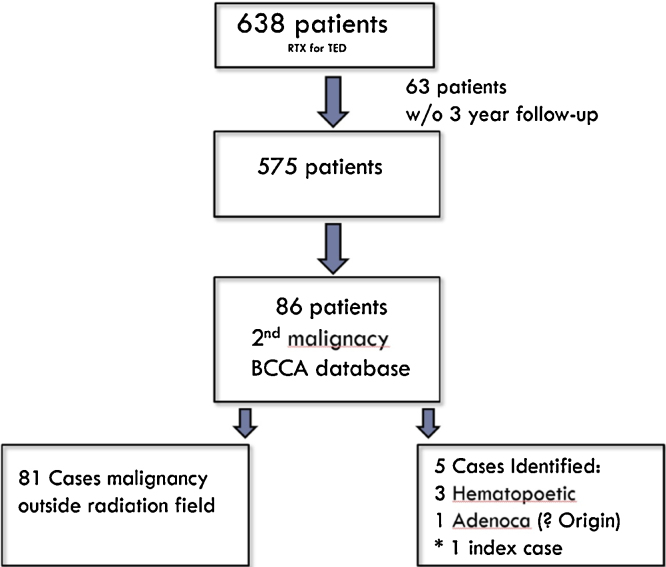

In our institutional review there were a total of 638 patients who received radiation therapy for TED from 1984 to 2010. This consisted of 575 patients (155 male and 420 female) with at least 3 years of follow-up since their radiation (see Fig. 5). The majority of patients received radioiodide therapy in addition to their radiation therapy. The mean follow-up was 14 years, the median follow-up was 10 years, with the longest follow-up at 29 years. The incidence rate of meningioma in our cohort was 13.23 cases per 100,000 person-years.

Fig. 5.

Patient selection and inclusion flow diagram for retrospective review of the BCCA database.

Of these patients, 86 (21 male and 65 female) were identified who also had a subsequent malignancy. 81 of these were outside the area of radiation on chart review (29 lung, 23 colon, 22 breast, 1 endometrial, 1 cholangiocarcinoma, 2 squamous cell carcinoma of skin outside of involved area, 1 basal cell carcinoma and 2 melanoma). Five patients were selected for further review and included: 1 adenocarcinoma not otherwise specified (breast primary on chart review and then excluded), 1 case of acute myeloid leukemia, 1 B cell lymphoma, 1 essential thrombocytopenia, and 1 meningioma (index case).

This leads to a calculated risk in our population of developing a radiation-induced meningioma after TED with at least 3 years of follow-up of: 1/575 = 0.17%; if we include the hematopoetic malignancies as secondary malignancies the risk for any secondary malignancy becomes: 4/575 = 0.7%. The incidence rate of meningioma in our population was 13.23 cases per 100,000 person-years of follow-up.